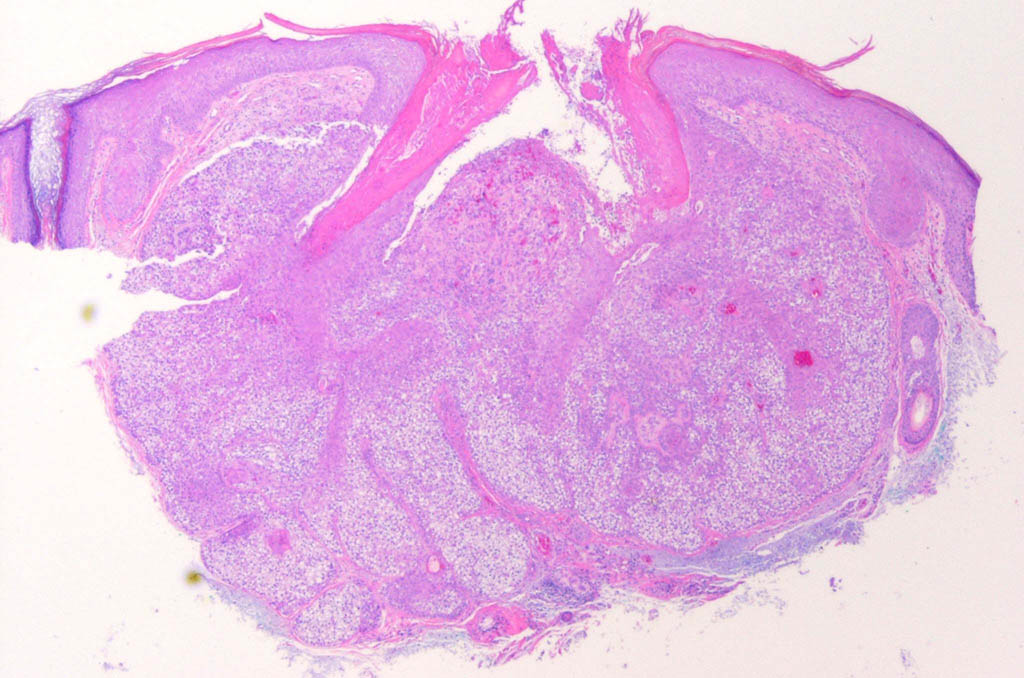

Trichilemmoma =ورم غمد جذر الشعرة